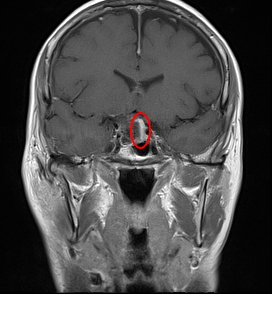

W toku diagnostyki w SOR wykonano badanie CT głowy, w którym uwidoczniono podejrzenie guza w obrębie siodła tureckiego wyrastającego ponad jego ograniczenia anatomiczne w stronę zbiornika skrzyżowania wzrokowego.

W badaniu MRI potwierdzono wstępne rozpoznanie – inwazyjnego makrogruczolaka przysadki (PitNET), który wyrastał ponad przeponę siodła (wypustkę opony twardej ograniczającą siodło tureckie od góry, przez którą przechodzi lejek przysadki do samego gruczołu), w okolicę nadsiodłową z wyraźną prawostronną lateralizacją w stronę bruzdy bocznej prawej.

Masa nowotworowa wyraźnie uciskała nerw wzrokowy, obrastała tętnicę szyjną wewnętrzną prawą dookoła jej obwodu. W panelu hormonalnym nie stwierdzono znaczących odchyleń poza nieznaczną hiperprolaktynemią. Chora została zakwalifikowana do leczenia operacyjnego.

Najczęściej stosowaną procedurą chirurgiczną jest resekcja guza drogą endoskopową przezklinową przez nos. W tym przypadku boczne granice nowotworu przekraczały nerw wzrokowy, wrastały w stronę środkowego dołu czaszki co sprawia trudności w usunięciu tego fragmentu nowotworu tą metodą.

W związku z tym pacjentka została zoperowana dostępem nadoczodołowym z cięcia skórnego przez brew. Jest to jedna z metod chirurgicznych, która mieści się w obrębie minimalnie inwazyjnych procedur czaszkowych (tzw. keyhole approach), o doskonałych efektach kosmetycznych. Guza usunięto w całości, zarówno z okolicy nadsiodłowej, jak i z dołu przysadki. Zachowano gruczoł przysadki i lejek przysadki bez konieczności trwałej suplementacji hormonalnej.